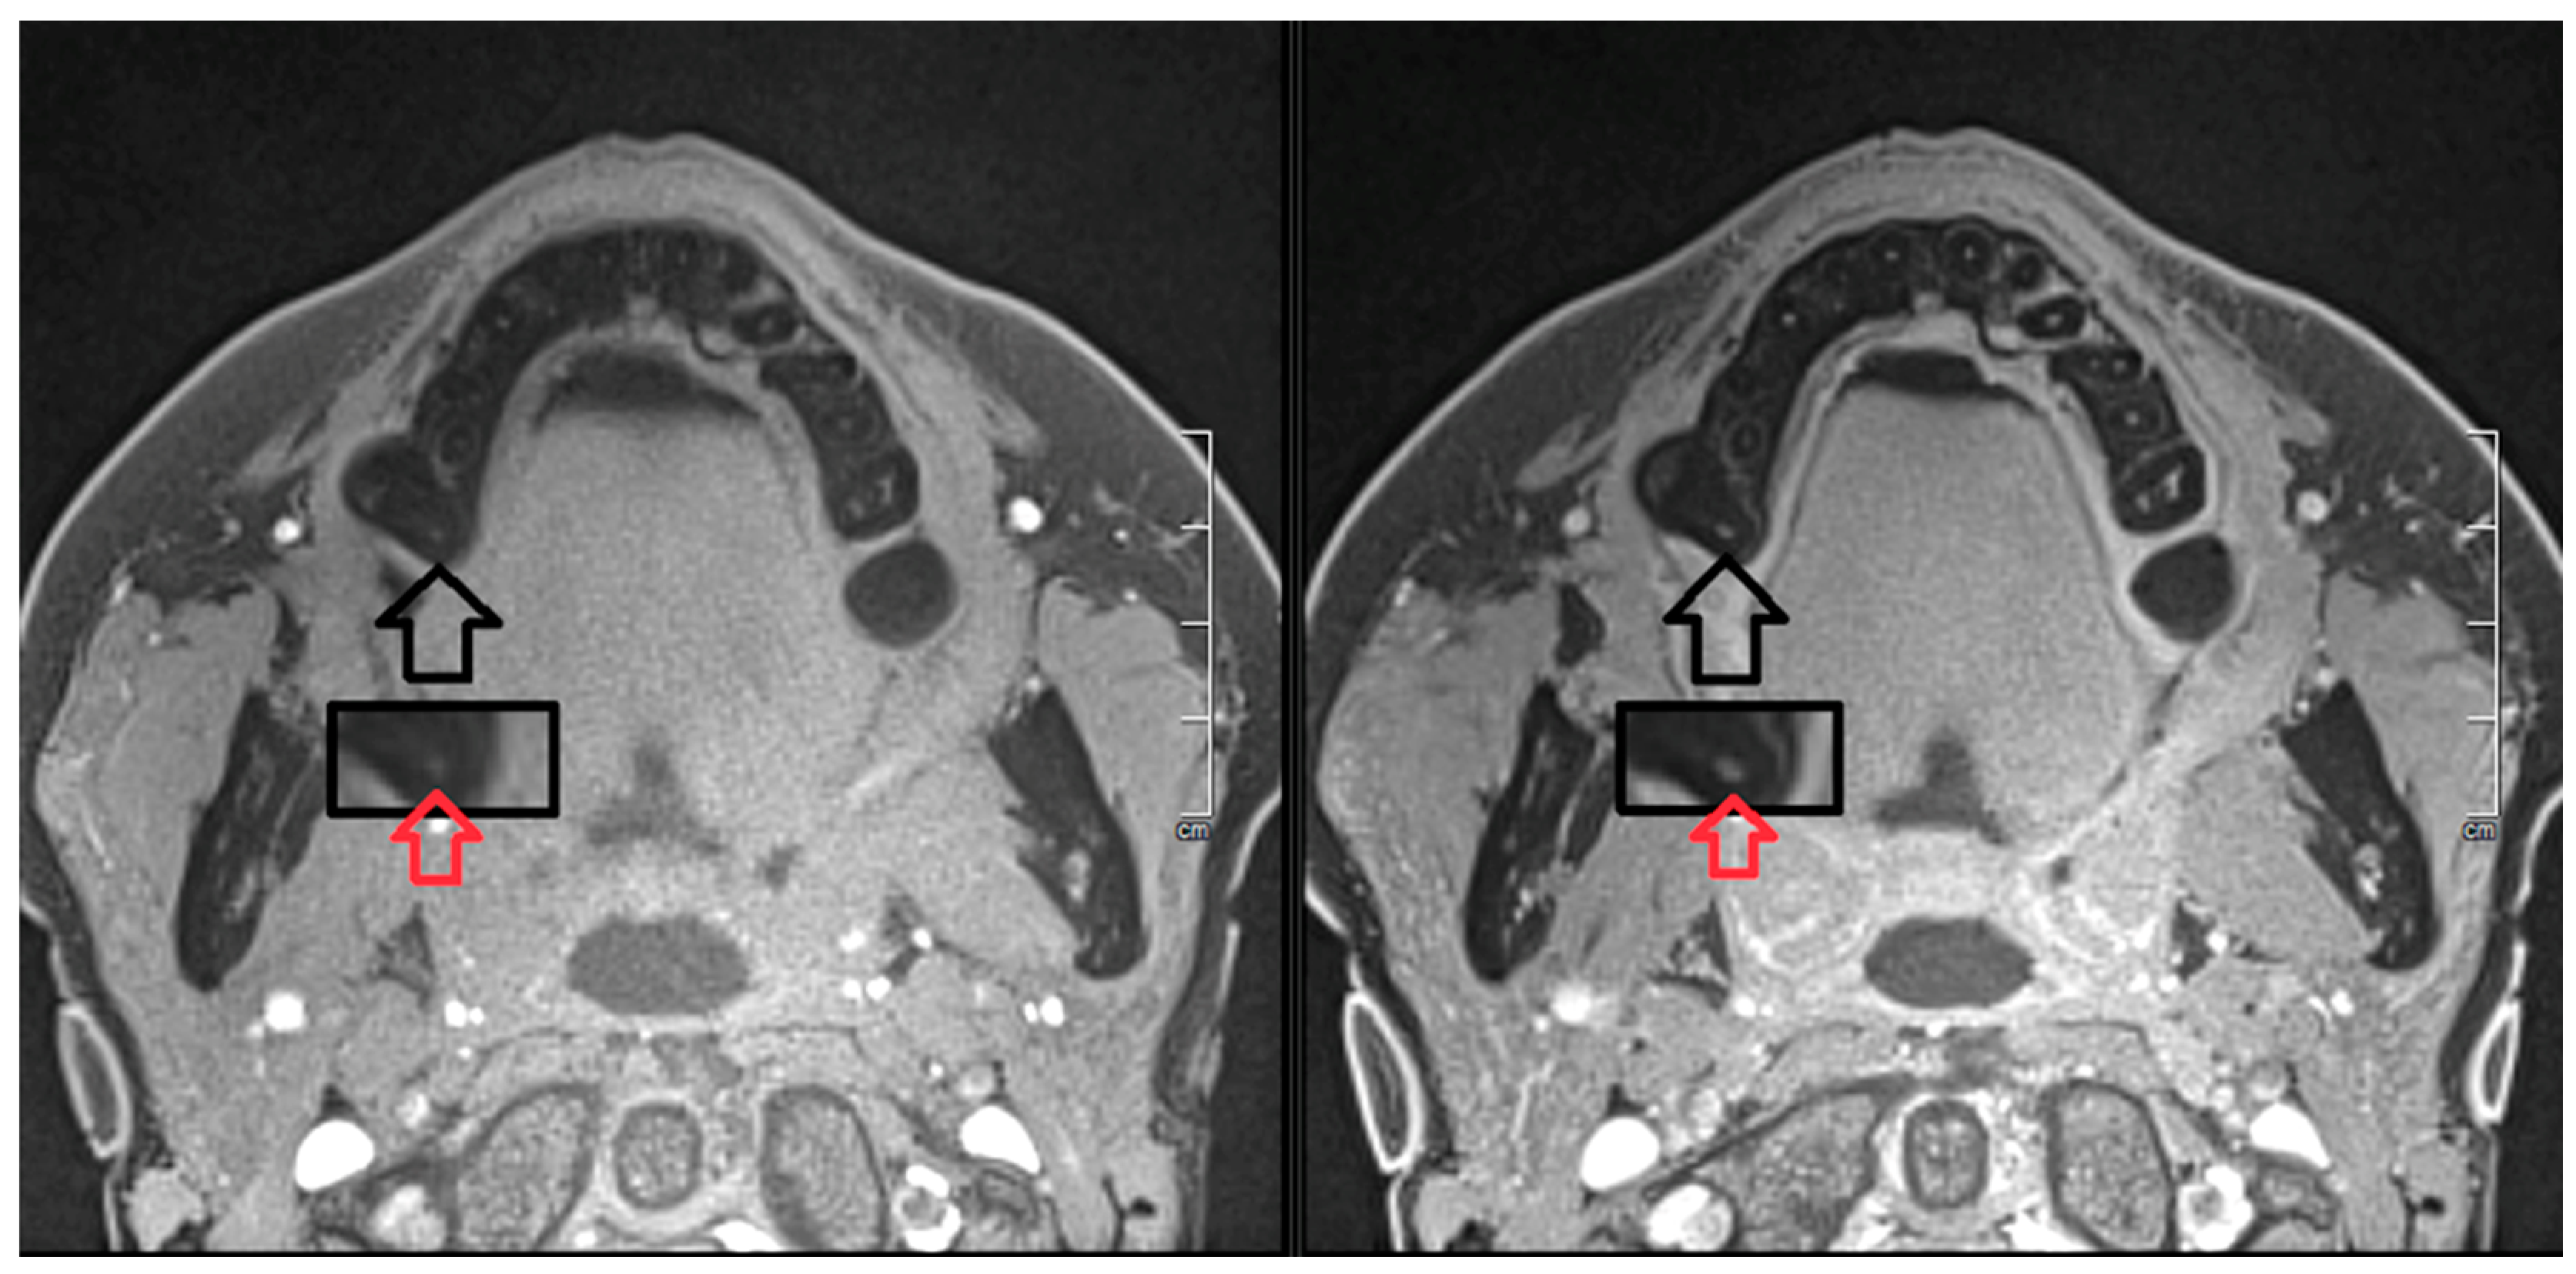

2. Report